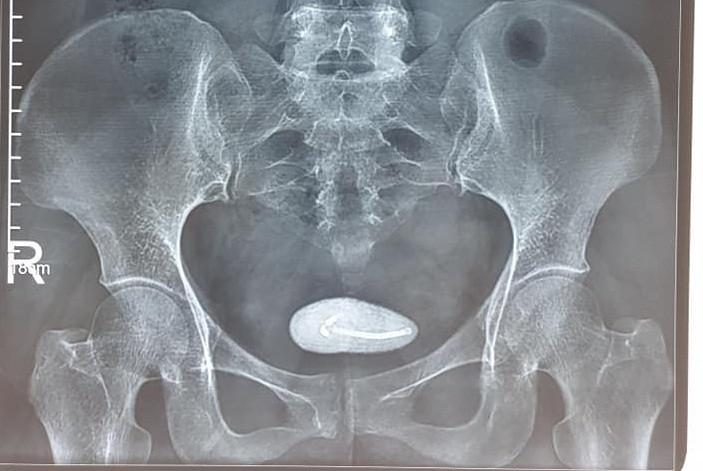

Sau khi thăm khám và làm các xét nghiệm cận lâm sàng, Bác sỹ chẩn đoán bệnh nhân đã bị vòng tránh thai lạc vào bàng quang, dần dần hình thành sỏi bàng quang, kích thước (5x6)cm.

| Hình ảnh vòng tránh thai đi lạc tạo sỏi trong bàng quang - Ảnh: BVCC |

Th.S BS. Ma Ngọc Ba - Trưởng khoa Ngoại Thận - Tiết niệu cho biết: “Bệnh nhân đã được áp dụng phương pháp tán sỏi bàng quang ngược dòng bằng laser hiện đại. Sỏi được tán vụn bằng laser, sau đó vòng tránh thai được ra khỏi cơ thể mà không phải mổ mở, bệnh nhân hồi phục sức khỏe sớm, thời gian nằm viện ngắn”.